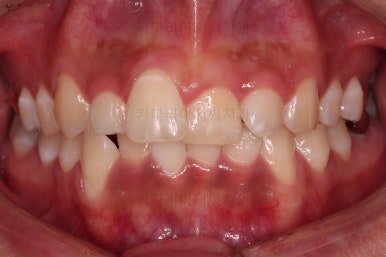

초진 시, 입 안의 모습이에요.

위아랫니가 삐뚤고 교합이 약간 맞지 않네요.

입 안만 보면 심플하게 교정하면 되겠다 싶지만, 문제는 다른 곳에 있었어요.